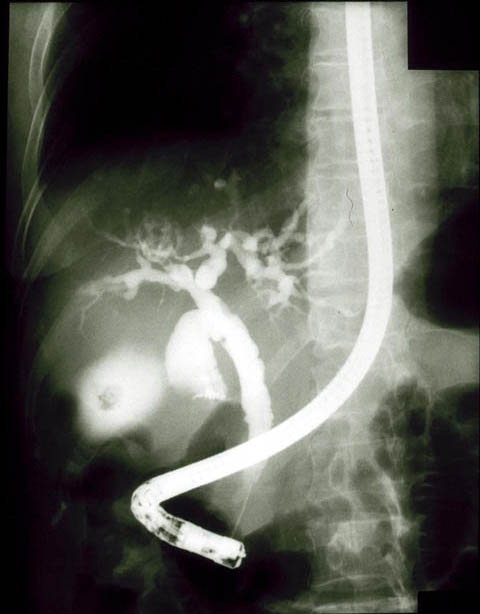

ERCP‚ΜŠŒ©‚Ε‚ΝŠΜ“ΰ’_ŠΗ‚Μcystic‚ΘŠg’£Aγ•”’_ŠΗ‚ΜŒ‡‘ΉiƒrƒŠƒ‹ƒrƒ“Œ‹Ξj‚Ζ’_”X“ΰ‚ΙŒ‹Ξ—l‚Μ‰A‰e‚ͺ”F‚ί‚η‚κ‚ιB